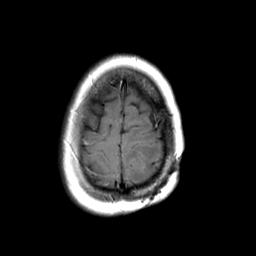

MR Study #3 -- Slice #46